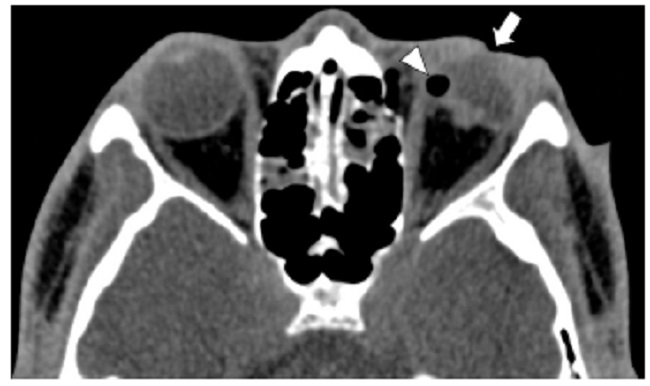

Las calcificaciones oculares y el material médico se pueden confundir con cuerpos extraños u otras lesiones orbitarias1. Las localizaciones típicas de las calcificaciones permiten diferenciarlas de cuerpos extraños hiperdensos. Las más frecuentes son las calcificaciones trocleares, las placas esclerales, las drusas del nervio óptico y la ptisis bulbi. Las primeras tienen localización superomedial dentro de la órbita (Fig. 13), en la tróclea del músculo oblicuo superior, aunque se pueden observar en todas las edades, hay mayor prevalencia de calcificaciones trocleares en pacientes con enfermedades autoinmunes y niveles elevados de fosfatasas alcalinas. Las placas esclerales se localizan en los sitios de inserción de los músculos rectos medial y lateral (Fig. 14) y son más comunes en los pacientes ancianos. Las calcificaciones que ocurren cerca del disco óptico se conocen como drusas del nervio óptico (Fig. 15), las cuales se asocian a degeneración macular y pueden ser causa de pseudopapiledema benigno. La ptisis bulbi es una atrofia y calcificación del globo ocular como secuela de enfermedades infecciosas, inflamatorias o traumáticas previas (Fig. 16) (1,11. Los imitadores de lesiones abiertas del globo ocular incluyen las deformidades como coloboma, estafiloma y el globo ocular elongado por glaucoma o miopía (Fig. 17). Las masas orbitarias y los hematomas también pueden alterar el contorno del globo ocular y asociarse a calcificaciones o relacionarse con desprendimiento de retina (Fig. 18) (1,6,8,11.